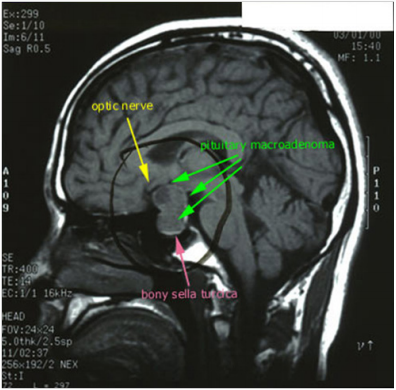

MRI of Head Nov. 01

1. A large pituitary tumor measuring 26x22mm isointense with brain, showing suprasellar extension, it shows calcifications and peripheral enhancement.

2. Brain, ventricles, & cisterns are normal, there is no shift of midline structures…

3. Conclusion: Pituitary Adenoma with suprasellar Extension.

Tumor & Optic Nerve(literature’sreview)

Courtesy of Juliette Siegfried (www. brain-surgery. com).

A well-circumscribed mass is present within the expanded sellaturcica. This mass has suprasellar extension and demonstrates iso-intense signal on T1 weighted imaging, heterogeneous but predominantly low signal on T2 weighted imaging, and has predominantly peripheral enhancement, the lesion mildly bulges into the right cavernous sinus with no definite invasion. The optic chiasm is superiorly displaced by the mass and drapes over it. The lesion elevates anterior aspect of floor of the third ventricle without causing hydrocephalus.